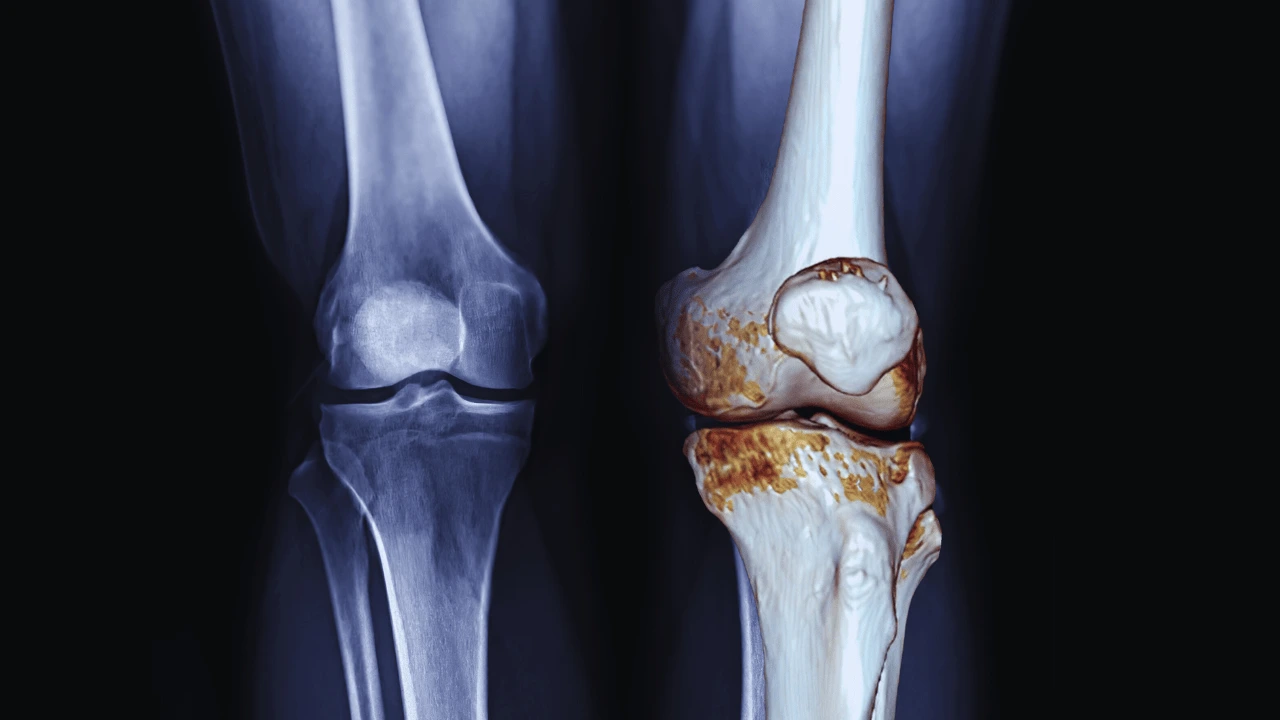

Knee Pain Behind and Around the Kneecap? You Might Have Patellofemoral Pain Syndrome

Read More